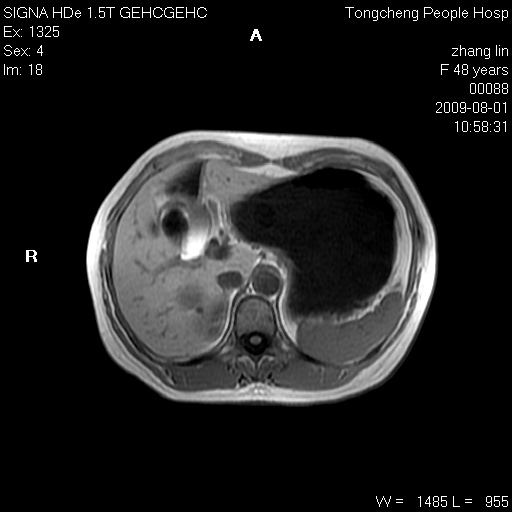

女,48岁。健康体检,彩超发现右肾占位性病变。平素健康。

临床诊断:右肾占位性病变,性质待定(囊肿?肿瘤?)。

上中腹部mr平扫+增强扫描,图像如下:

右肾上极见一类圆形病灶,t1wi呈等信号t2wi呈等高混杂信号,三期增强无强化,边界清---考虑囊肿出血。

同反相位均表现为等信号,病变无强化,考虑含蛋白的囊肿可能,弥散加权相或许有些帮助,